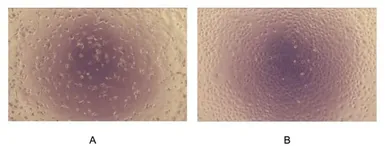

GTX04319-pro Functional Assay Image

Cell proliferation effect of GTX04319-pro Mouse TGF beta 1 protein, His tag (active) 48h observed by inverted microscope.

(A) A549 cells cultured in DMEM, stimulated with 12.5μg/mL TGF-β1

(B) Unstimulated A549 cells cultured in DMEM